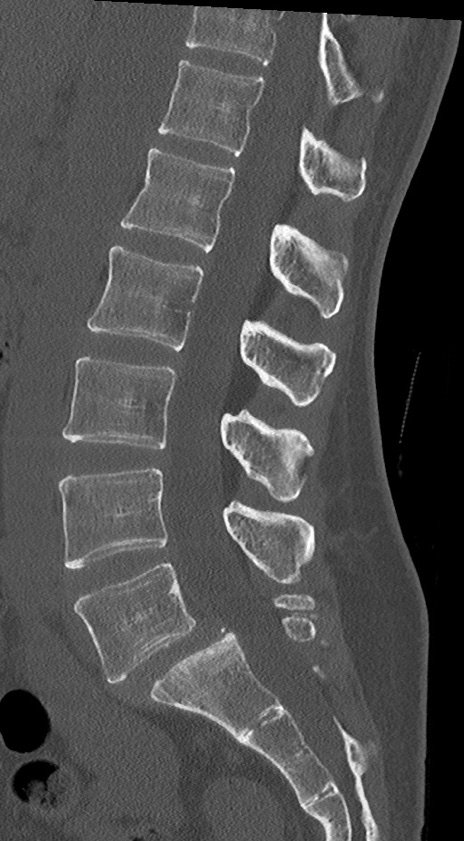

【整形】TIPS症例4 腰椎CT(矢状断像)

腰椎CT